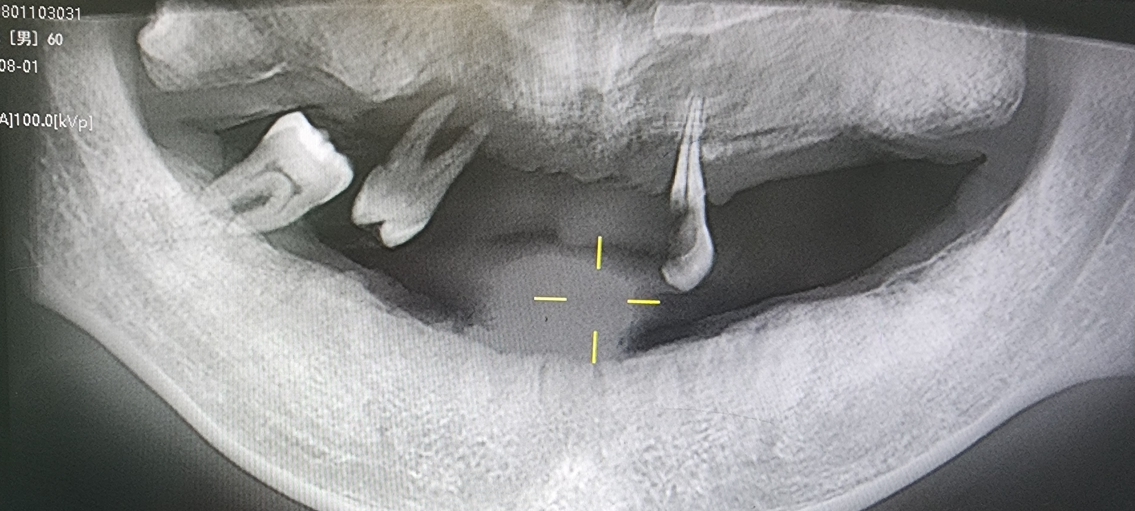

2).Subgingival Calculus (Star of This Article): Found below the gingival margin, within periodontal pockets, and tightly attached to the root surface. Invisible to the naked eye, it can only be detected by dentists using a periodontal probe.

3.Characteristics: Darker in color (dark brown or blackish-green), harder in texture, firmly adhering to tooth roots like cement, and highly destructive to periodontal tissues.

Periodontal Surgery: For severe cases with extremely deep periodontal pockets (>5mm), surgical procedures like periodontal flap surgery may be required for thorough debridement.